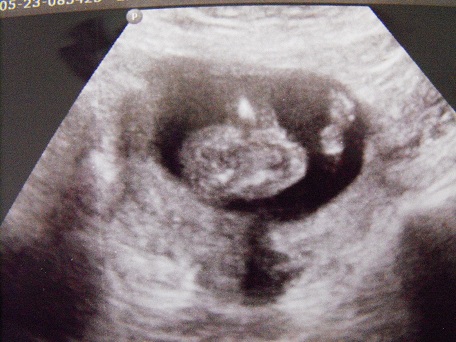

15w1d Ultrasound....What do you think?

So I went in for my regular ob visit and my doctor (not a tech my actual ob) decided to do an extra ultrasound. She did it just to see what the gender was she looked a bit and then asked me if I really wanted to know what she thought, I of course told her yes, and she said she thinks it is a girl. She showed me the parts again and pointed out the three dots and then said she was also not finding any thing else poking out. She then went on with the u/s looking at the rest of the baby and then went back to the gender area and said again yeah girl but then she added the "its still early though and I shouldn't go buy pink just yet but she is pretty certain it is a girl". As always the pictures I got were not the best I just want to know what others think..Attachment 2886Attachment 2887